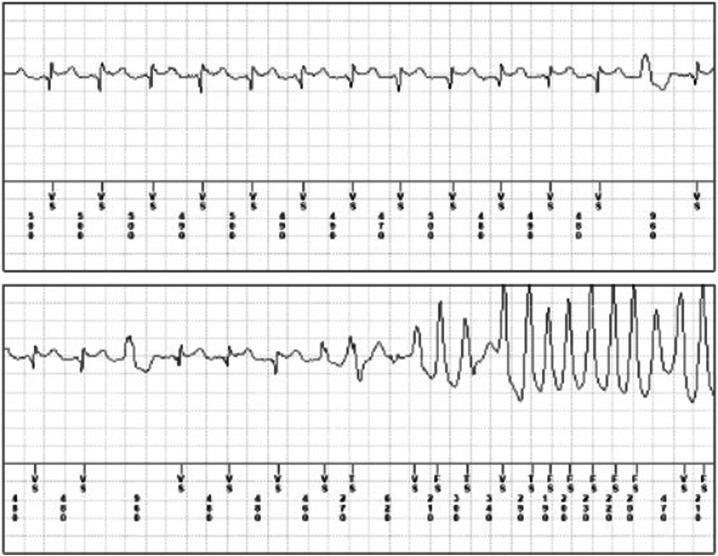

药物不良反应(ADR)是发病和死亡的一个重要且常见的原因。ADR可能与多种药物有关,包括抗惊厥药、麻醉药、抗生素、抗逆转录病毒药、抗癌药和抗心律失常药,并且可能累及每个器官或系统。由于ADR的临床异质性和复杂性,其病因仍知之甚少。在这种情况下,ADR的遗传易感性不仅在抗癌化疗中,而且在许多其他医学领域中都是一个新出现的问题,包括葡萄糖-6-磷酸脱氢酶(G6PD)缺乏症导致的溶血性贫血、再生障碍性贫血、卟啉症、恶性高热、表皮组织坏死(莱尔综合征和史蒂文斯-约翰逊综合征)、癫痫、甲状腺疾病、糖尿病、长QT综合征和 Brugada综合征。已经证明基因突变在ADR发病机制中对于剂量依赖性或非剂量依赖性反应都起作用。在这篇综述中,我们介绍了ADR遗传背景的最新情况,其表型表现涉及血液、肌肉、心脏、甲状腺、肝脏和皮肤疾病。这篇综述旨在说明遗传学在预防ADR以及优化许多常用药物的安全治疗应用方面日益增长的有用性。从这个角度来看,ADR可能成为一种不良的“压力测试”,从而导致对遗传决定疾病的新诊断。因此,在ADR检查中更广泛地使用药物遗传学检测将导致对以前未被怀疑疾病的新临床诊断,并提高治疗的安全性和有效性。通过新的实验室技术以及未来人工智能的应用来改善基因型-表型相关性,可能会带来个性化医疗,能够预测ADR,从而为每个患者选择合适的化合物和剂量。

Brugada syndrome genetics is associated with phenotype severity.Brugada 综合征遗传学与表型严重程度相关。

Assessing QT interval in COVID-19 patients:safety of hydroxychloroquine-azithromycin combination regimen.评估 COVID-19 患者的 QT 间期:羟氯喹-阿奇霉素联合方案的安全性。